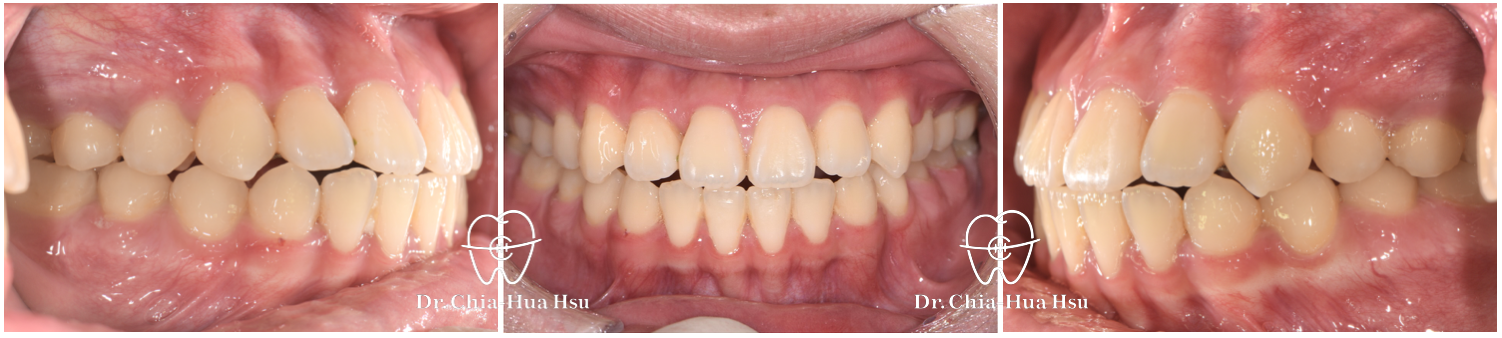

治療前

治療後